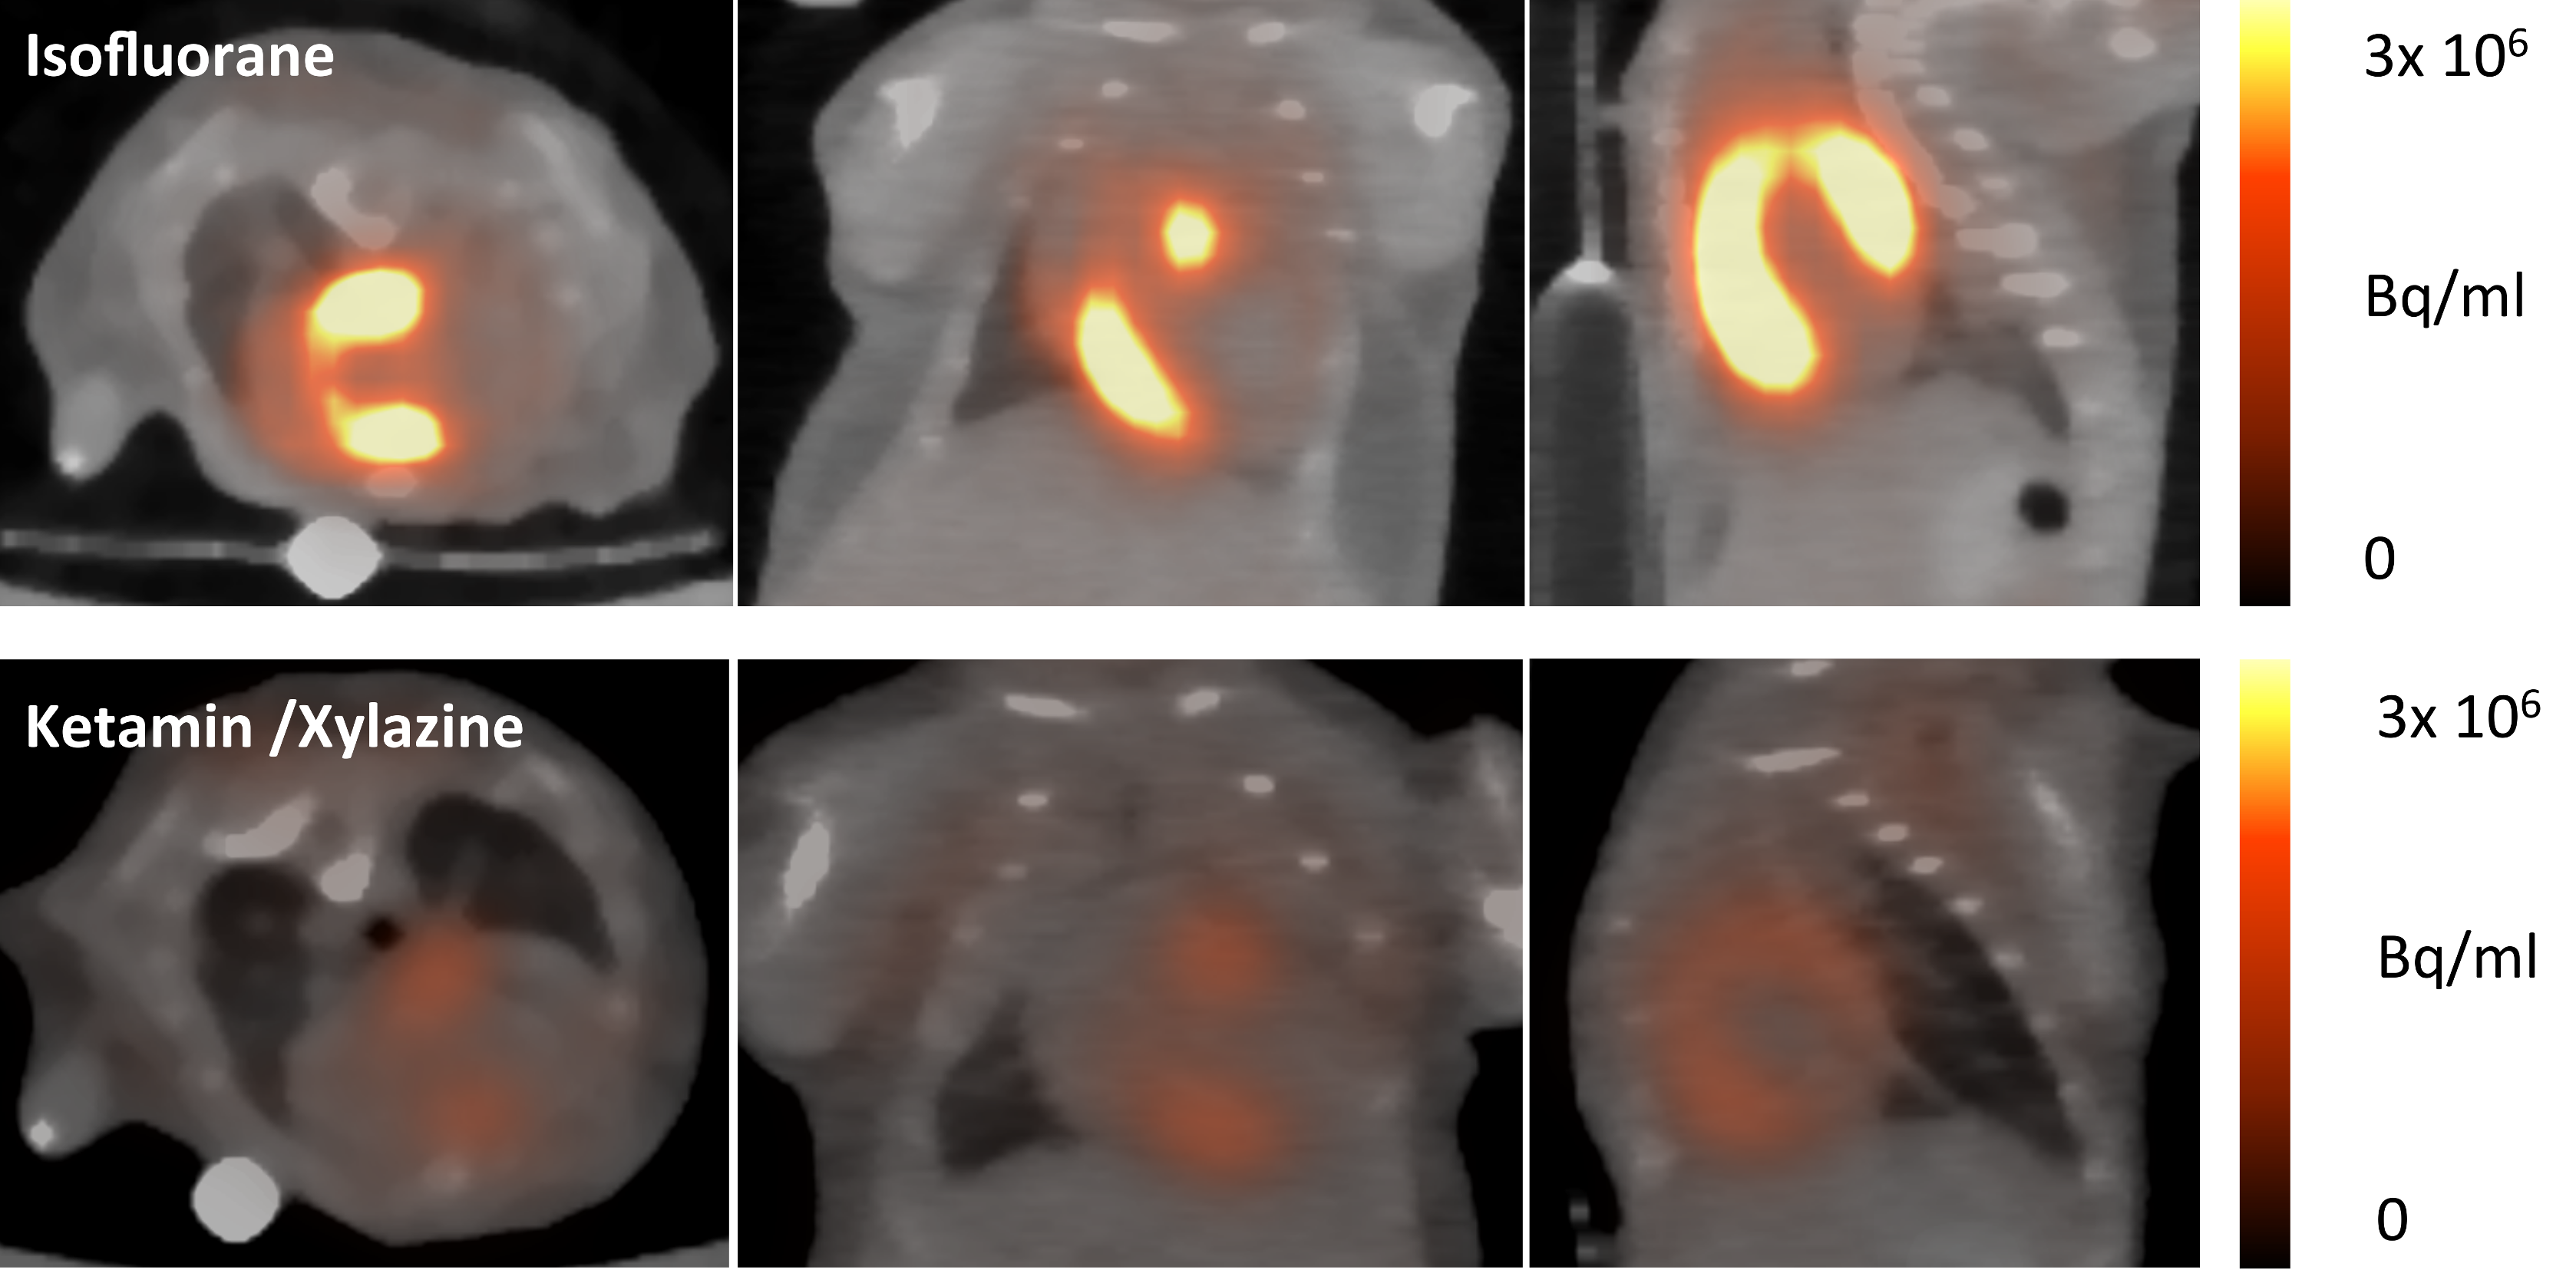

3.2. Impact of Anaesthesia on the FDG-Uptake Pattern in the Infarcted Heart